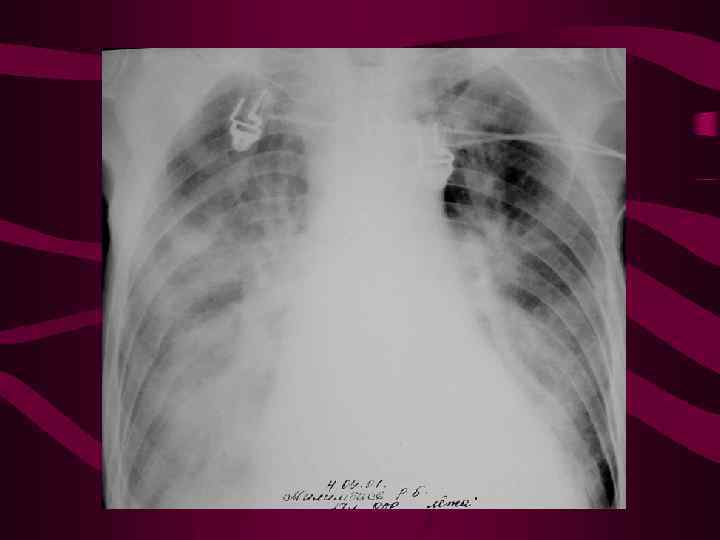

4 - альвеолярный отек легких Изменения соответствуют среднему давлению в левом предсердии свыше 35 мм рт. ст. На фоне венозного застоя с признаками интерстициального отека определяются множетсвенные сливающиеся, разной величины очаговые тени в легких за счет скопления эксудата в альвеолах. Очаговость имеет неравномерную интенсивность и нечеткие очертания, может быть симметричной, двухсторонней, но может быть и односторонней. Нередко выпот в плевральных полостях.

4 - альвеолярный отек легких Изменения соответствуют среднему давлению в левом предсердии свыше 35 мм рт. ст. На фоне венозного застоя с признаками интерстициального отека определяются множетсвенные сливающиеся, разной величины очаговые тени в легких за счет скопления эксудата в альвеолах. Очаговость имеет неравномерную интенсивность и нечеткие очертания, может быть симметричной, двухсторонней, но может быть и односторонней. Нередко выпот в плевральных полостях.

Альвеолярный отек слева

Альвеолярный отек слева